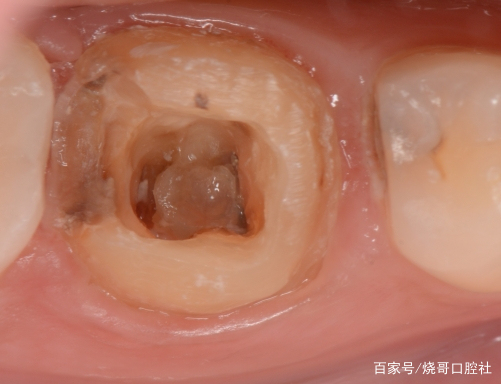

1、口腔鏡檢查:通過口腔鏡檢查,可以清晰地觀察到牙齒表面的牙洞以及牙洞內的情況,醫(yī)生可以判斷牙洞是否已深入牙髓,并評估病情嚴重程度。

2、探診檢查:使用牙科探針檢查牙洞周圍組織的健康狀況,了解牙洞深度及與牙髓的關系。

X光檢查是判斷牙齒牙洞是否深入牙髓的重要手段之一,通過X光檢查,可以清晰地看到牙齒內部結構,了解牙洞的位置、大小及深度,從而判斷牙洞是否已侵犯到牙髓。